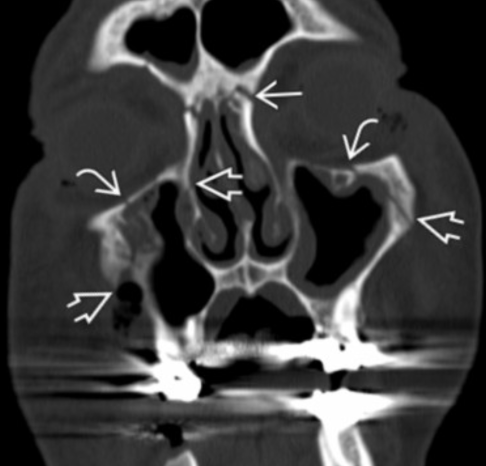

LeFort Type III

- Passe par l’arcade zygomatique et les orbites

- Détache l’ensemble de l’os facial (dissociation cranio-faciale)